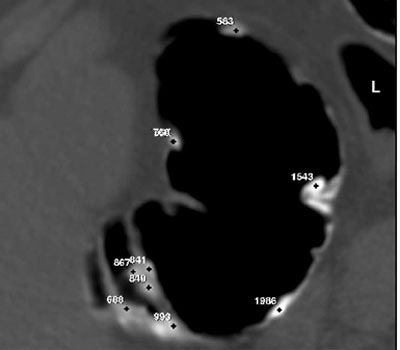

"The first group had 3 doses of 350 ml of a 2.1% barium suspension. The second group started with a 4% suspension, followed by 2 doses of the 2.1% suspension. And finally, the third group was prepared for 3 days: the first day 3 doses of 50 mls of a 4% suspension, followed the next day by the same thing as Group 1. The best results (highest densities) were obtained in Group 3."

| Sample Hounsfield unit meaurements of barium-tagged fecal matter in patient groups 2 (above) and 3 (below). The highest HU intensities were obtained in the three-day regimen followed by patient group 3. Images courtesy of Dr. Philipe LeFere. |